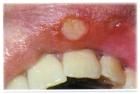

粘膜病在我们的日常生活中,存在的几率是比较频繁的,它包括的范围也是比较广泛的,几乎所有的人都存在有粘膜病的侵袭,只是发生的程度有所不同,下面就请北京京城皮肤医院,就粘膜病的一些发生特点为我们做详细的服务。

四是有病要早治。扁平苔藓属于是癌前发生的病变,粘膜科在临床中每年都发现一些因失治或误治发生癌变的患者,所以一旦患了扁平苔藓就要抓紧进行治疗。要把癌症消灭在萌芽之中,以免给自身带来更加大的伤害。